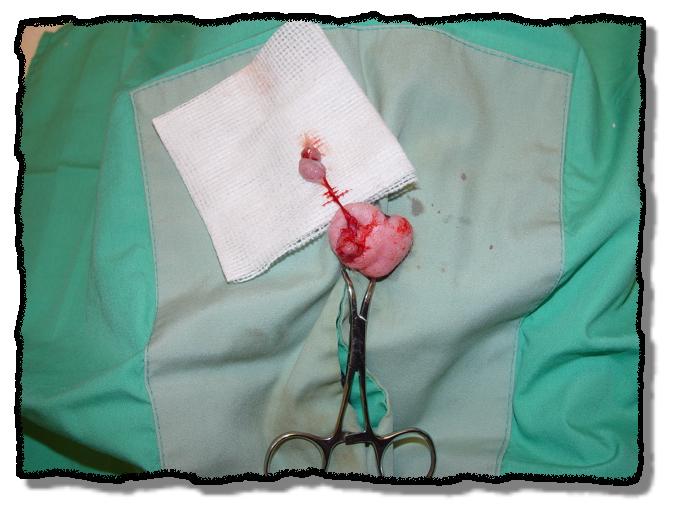

NEUTERING A MALE POSSUM

The scrotum is easily visualized and is attached to the body by a thin stalk.

Skin incision made over each testis. (Note: procedure repeated on opposite side)

Ligamentous attachments to the testis are freed and the vasculature is isolated.

Double-ligation of the testicular vessels.

Skin incision closed with a single subcutaneous cruciate stitch.